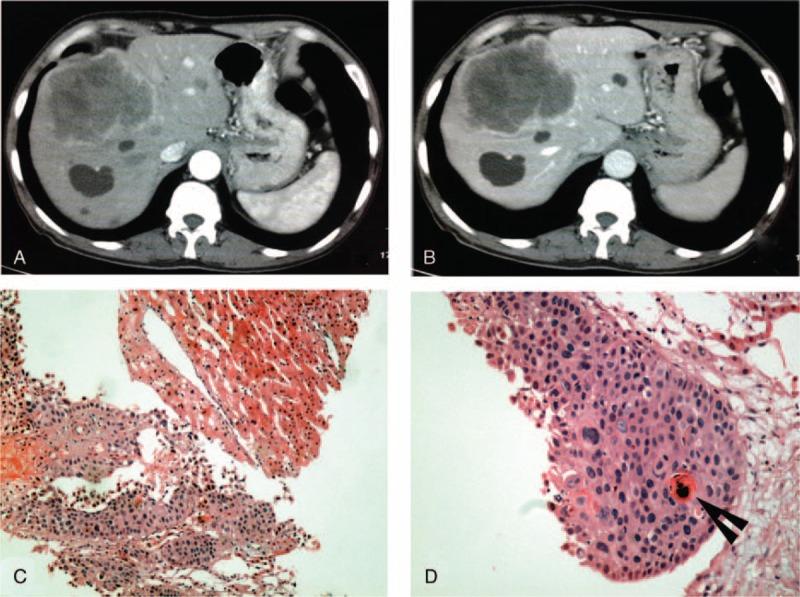

Primary squamous cell carcinoma (SCC) of liver is rare, and its prognosis is extremely poor. This study aims at reviewing the clinical data of all pathologically diagnosed liver cancer in our institute, and discussing the clinical presentation, diagnosis, treatment, and prognosis of our cases of SCC and the literatures reported previously. All the patients undergoing liver surgery or biopsy for liver cancers from 2002 to 2013 in our hospital were reviewed, and the liver specimens were examined pathologically. A literature search for case reports of primary SCC of liver published until December 31, 2014, was performed on PubMed, MEDLINE, Scopus Elsevier, Cochrane, and Google Scholar. The primitive data of the case reports were all included and analyzed if available. From January 2002 to October 2013, 2210 cases of liver cancer were diagnosed pathologically in our hospital. Among, 4 cases (0.2%) were diagnosed as primary SCC of liver. All were negative for hepatitis B infection, but present with liver cyst and/or hepatolithiasis. One patient underwent radical resection, but died of tumor recurrence 18 months postoperatively. One patient received transcatheter arterial chemoembolization and 1 patient received laparotomy and alcohol injection, but died 9 and 4 months after surgery, respectively. The last patient received only biopsy and supportive treatment, and finally died of tumor metastasis 6 months later. From 1970 to 2014, 31 cases of primary liver SCC have been published in English previously. Thirty one cases and the 4 cases in the present study were included. The average age of the patients were 54 years (range 18-83), with a male to female ratio of 19:16. Twenty patients had liver cysts, 7 had bile duct stones, and 2 cases had both. Patients undergoing radical surgery had better prognosis than those undergoing palliative treatments (median survival 17 vs 5 months, P = 0.005, log-rank test). Patients with liver cysts seemed to have worse prognosis than those with bile duct stones (median survival 7 vs 18 months, P = 0.090, log-rank test). Primary liver SCC seems to be mostly originated from liver cyst or hepatolithiasis. Radical surgery should be firstly recommended, although the prognosis might be unfavorable.

原发性肝癌(SCC)极为罕见,其预后极差。本研究旨在回顾我院所有经病理诊断的肝癌临床资料,探讨我院原发性肝癌病例的临床表现、诊断、治疗及预后,并与既往报道的文献进行讨论。回顾了我院2002年至2013年期间所有因肝癌接受肝脏手术或活检的患者,并对肝脏标本进行了病理检查。在PubMed、MEDLINE、Scopus Elsevier、Cochrane和谷歌学术上检索截至2014年12月31日发表的原发性肝癌病例报告。如果有可用的病例报告原始数据,则全部纳入并进行分析。2002年1月至2013年10月,我院经病理诊断肝癌2210例。其中,4例(0.2%)被诊断为原发性肝癌。所有患者乙肝感染均为阴性,但均伴有肝囊肿和/或肝内胆管结石。1例患者接受了根治性切除,但术后18个月死于肿瘤复发。1例患者接受了经动脉化疗栓塞术,1例患者接受了剖腹手术及酒精注射,但分别于术后9个月和4个月死亡。最后1例患者仅接受了活检及支持治疗,最终于6个月后死于肿瘤转移。1970年至2014年,英文文献中此前已发表31例原发性肝癌病例。纳入了31例病例及本研究中的4例病例。患者平均年龄54岁(范围18 - 83岁),男女比例为19:16。20例患者有肝囊肿,7例有胆管结石,2例两者均有。接受根治性手术的患者预后优于接受姑息性治疗的患者(中位生存期17个月对5个月,P = 0.005,对数秩检验)。有肝囊肿的患者预后似乎比有胆管结石的患者差(中位生存期7个月对18个月,P = 0.090,对数秩检验)。原发性肝癌似乎大多起源于肝囊肿或肝内胆管结石。尽管预后可能不佳,但应首先推荐根治性手术。